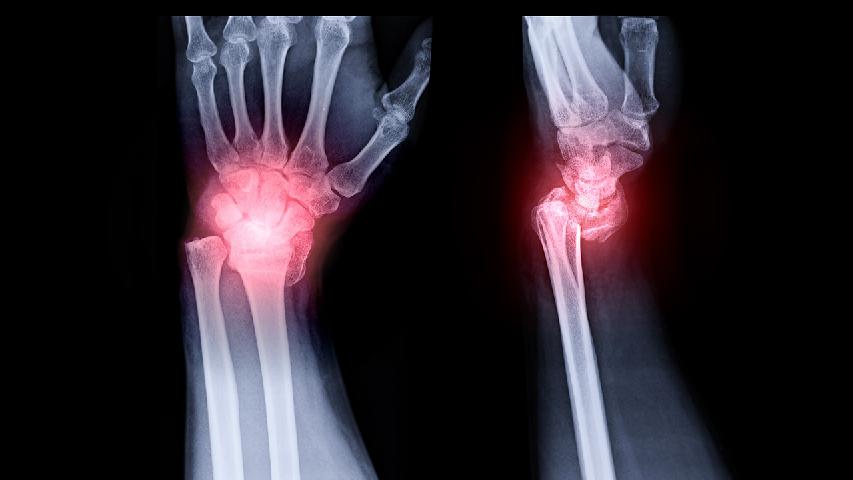

專家表示,在對(duì)類風(fēng)濕性關(guān)節(jié)炎患者進(jìn)行治療護(hù)理外,心理分析也是很重要的一點(diǎn),因?yàn)樾睦碇委熓侵委燁愶L(fēng)濕性關(guān)節(jié)炎的心理基礎(chǔ)。那么下面就由專家為我們介紹一下,對(duì)類風(fēng)濕性關(guān)節(jié)炎的患者的心理分析。專家表示類風(fēng)濕性關(guān)節(jié)炎患者的心理治療也很重要